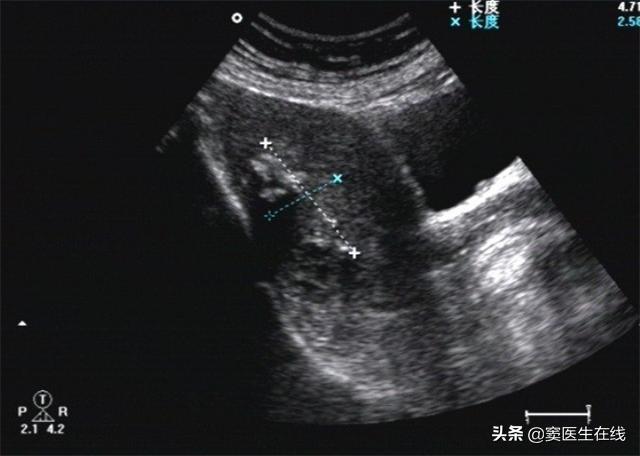

患者体温36.8℃、血压132/89、身高159cm、体重72kg。B超提示子宫内膜双层厚3.8mm,回声欠均匀。宫腔镜检查:子宫内膜厚,子宫内膜多个息肉样增生,宫颈外口可见一直径3cm息肉样物脱出,表面不平整,质地脆。MRI检查提示符合子宫内膜癌并腹水表现,左侧卵巢体积增大。子宫内膜策划病理学检查提示为子宫内膜癌早期。